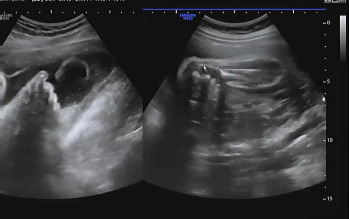

진료 순서가 되어 복부 초음파를 확인하였다. 여전히 햇님이는 자신의 건강함을 알리기 위해 초음파를 보는 내내 손을 이리저리 움직였다. 머리둘레, 복부둘레, 허벅지 뼈 길이를 측정하여 대략적인 체중을 확인하고 태아가 주수에 알맞게 크고 있는지를 확인했다. 머리둘레는 35주 차, 복부둘레는 34주 5일, 허벅지 뼈 길이는 33주 4일이라서 이상하다 생각했는데 평균적 수치는 주수에 알맞게 성장이라는 것을 듣고 안심했다. 2주 뒤인 37주 차에 내원을 예약했다.